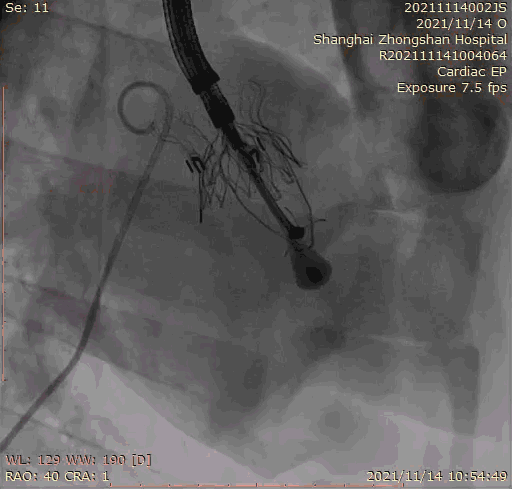

上海中山醫(yī)院葛均波院士、錢菊英院長、周達新教授、潘文志教授、潘翠珍教授、李偉教授共同完成此次臨床前研究。術(shù)后葛均波院士對Lux-Valve Plus的器械操作性能給予了高度評價,DSA和超聲影像也顯示出在本次研究中Lux-Valve Plus的安全性和有效性俱佳。

本次臨床前研究經(jīng)右側(cè)頸靜脈置入LuX-Valve Plus輸送系統(tǒng)可調(diào)彎鞘管,在DSA及超聲引導(dǎo)下將人工三尖瓣瓣膜植入到原有三尖瓣位置,利用獨特的錨定技術(shù)將人工瓣膜支架可靠固定在預(yù)定的位置。